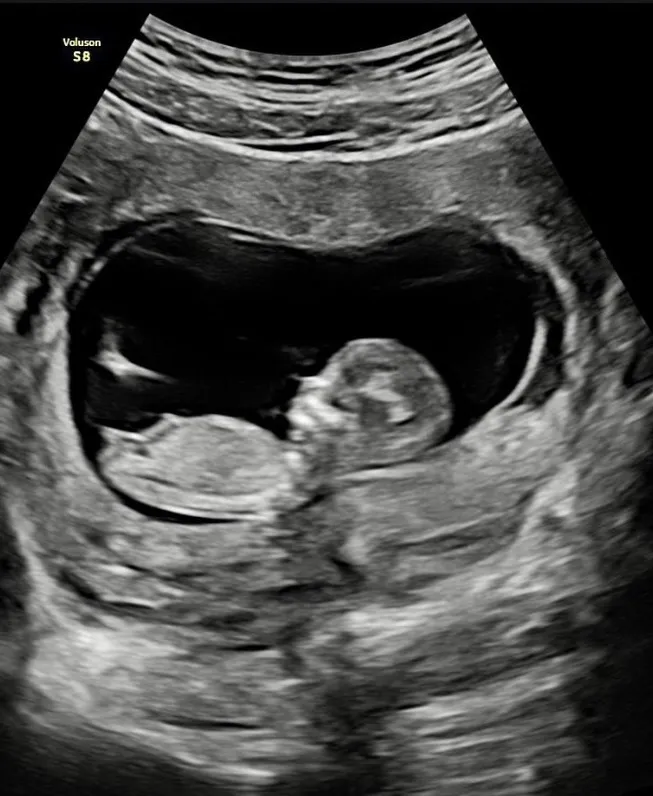

賴弘國秀出老婆超音波宣布二寶喜訊。翻攝賴弘國IG